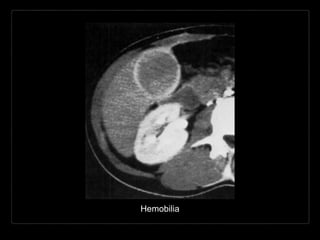

HEMOBILIA

Presencia de sangrado hacia el

árbol biliar y sangre en la bilis.

• Causas:

• trauma/biopsia

• enfermedad inflamatoria

• colelitiasis

• tumor

• anormalidades vasculares

Hallazgos por TC y RM

• contenido con densidad/intensidad hemática

• contenido heterogéneo de la vesícula biliar

• posición dependiente

• vesícula distendida con engrosamiento de su

pared

• + C

• reforzamiento de la pared vesicular

T2 Fat Sat - Hemobilia